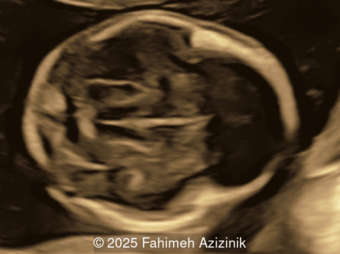

A 34-year-old woman, G2P1001, presented to our maternal fetal medicine unit at 30 weeks of gestation for a late fetal anatomic survey. The fetus was female with low-risk noninvasive prenatal testing. The following findings were observed.